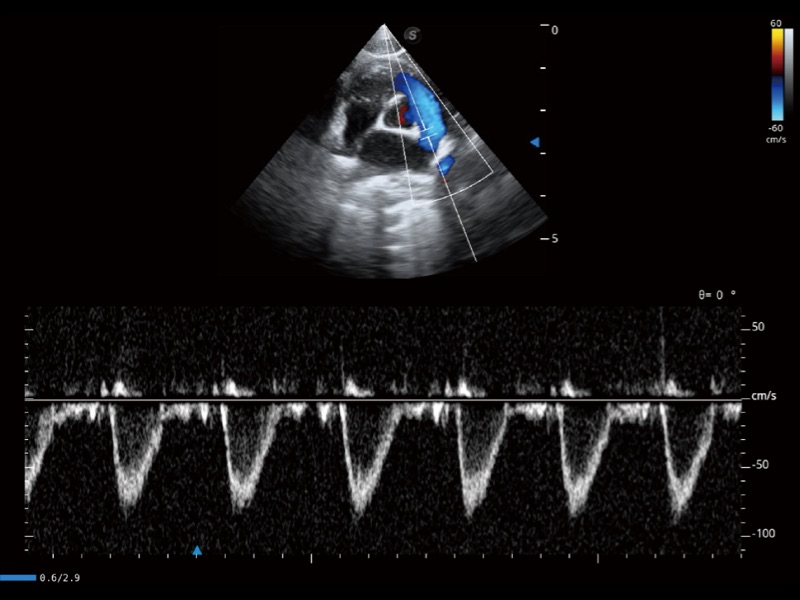

通过360度任意调节3条M型取样线,在同一心动周期上观察心脏不同位置的运动曲线,得到准确的心功能测量数据,有效评估心肌运动及左心室功能。

能够基于左心室壁追踪和辛普森法,自动计算射血分数,支持多个可移动点描迹,与手动测量相比,极大节省了动物医生的时间和精力。

当心脏测量结果超出正常范围时,可实时预警提示动物医生,减少疾病漏诊概率。